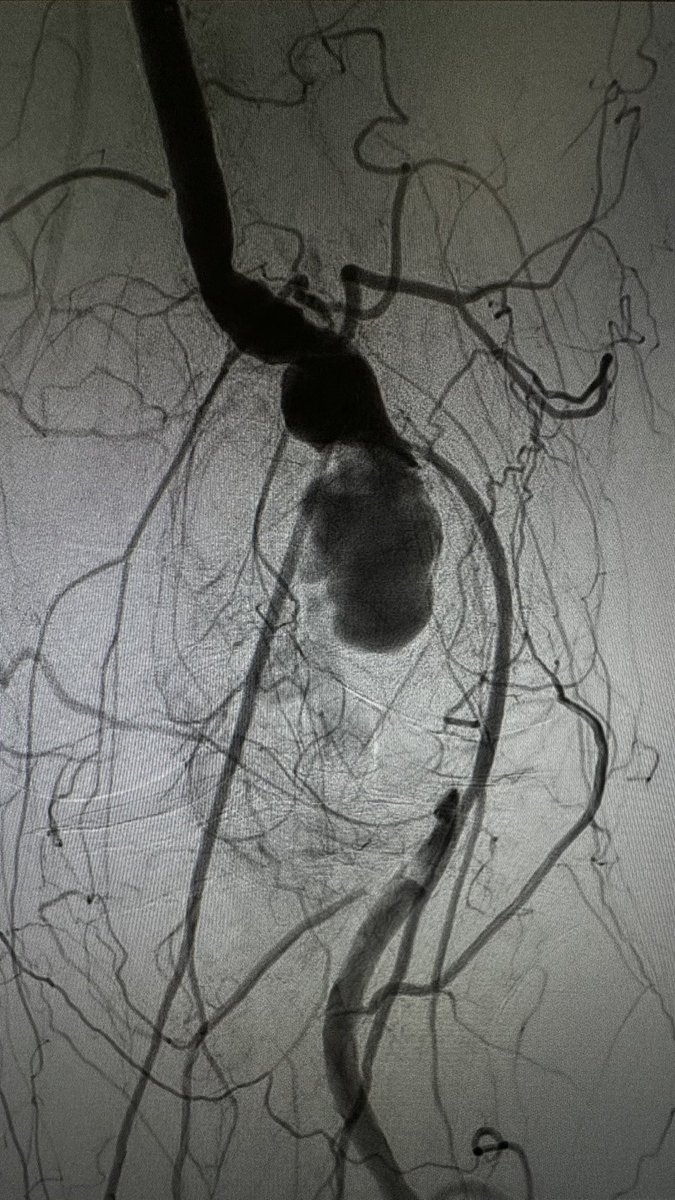

I hope this technique can help many colleagues who work with endovascular aortic arch repair. Useful for PMEGs, CMDs, Castor and TBE. Congratulations Miguel Fernandez! Thank you the whole team, and the reviewers!

doi.org/10.1177/152660…